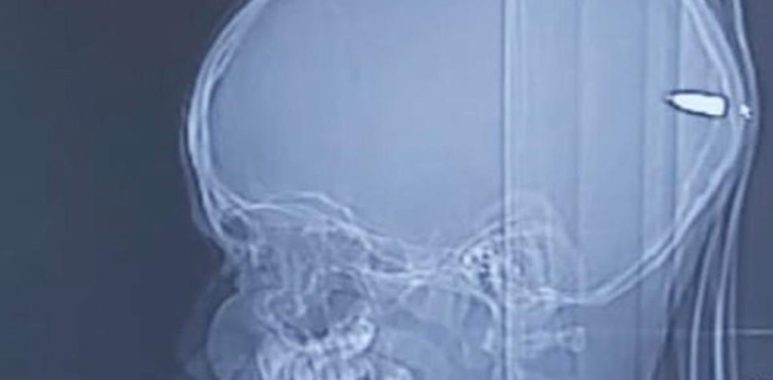

INSTAGRAM MARAVILLA ¿QUÉ PASÓ? La Brigada de Homicidios de Rancagua se encuentra trabajando junto al Laboratorio de Criminalística Regional de la PDI, el caso de una mujer que llegó hasta el hospital de la comuna con un proyectil balístico en su cabeza. TE PUEDE INTERESAR ➡️Tsunami de Covid-19: Ministerio de Salud reporta 24 mil casos … Continúa leyendo Mujer recibió balazo en el cráneo y no se dio cuenta